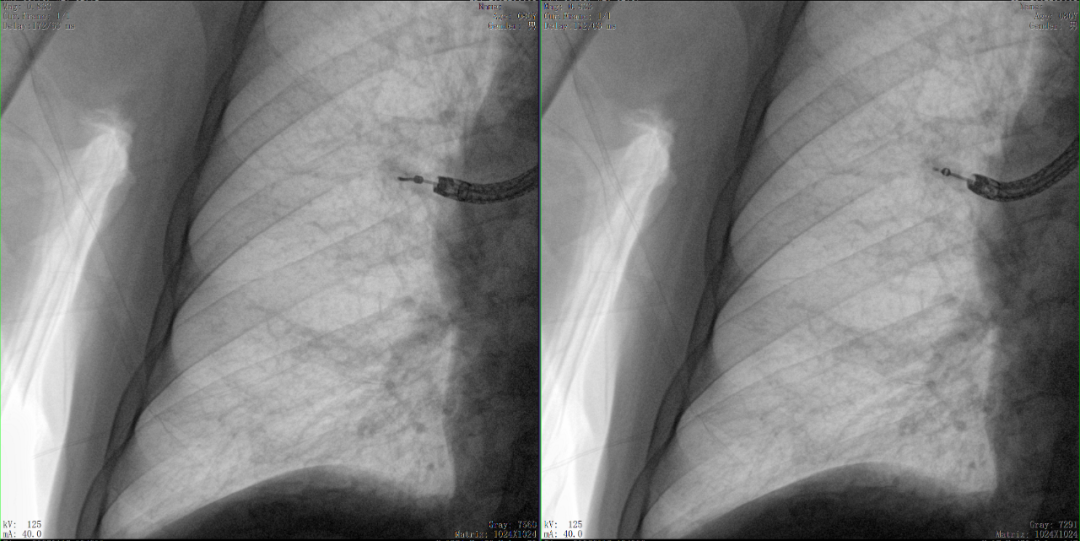

病例3:超聲支氣管鏡下肺活檢(80歲)

三維C形臂還可以創(chuàng)新性地應(yīng)用在呼吸介入領(lǐng)域。例如,在經(jīng)皮穿刺或經(jīng)支氣管鏡肺結(jié)節(jié)活檢、定位、消融等場景中,用于確認(rèn)工具是否到達(dá)病灶、消融范圍是否完全覆蓋病灶等。

二維影像無法準(zhǔn)確判斷工具是否到達(dá)病灶

三維各切面影像都顯示工具達(dá)到病灶內(nèi)

二維C形臂提供的影像存在固有局限性,其成像原理是基于單一方位的投影,導(dǎo)致深部解剖結(jié)構(gòu)信息缺失,且容易受到骨骼和組織的重疊干擾,使得部分病灶難以清晰顯示,甚至被掩蓋。相比之下,三維C形臂通過三維重建技術(shù),可以獲得類似CT的斷層掃描圖像,從而解決了二維影像的重疊問題。